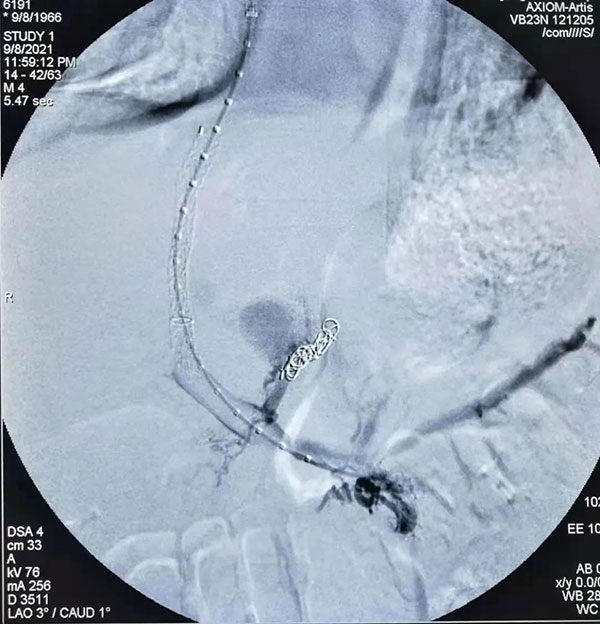

术中造影

介入科团队针对患者病情认真讨论后,与家属进行了充分沟通,决定行TIPS手术。手术中找到患者出血的胃底血管用带纤维的铂金圈进行栓塞,栓塞后效果满意,沿导丝引入TIPS覆膜支架系统释放支架,并用球囊反复扩张至凹迹消失,造影确认食道胃底静脉主干栓塞。由导管室护士陪同下安返病房。手术后牛先生生命体征平稳,意识清楚,非常感激在场医生。